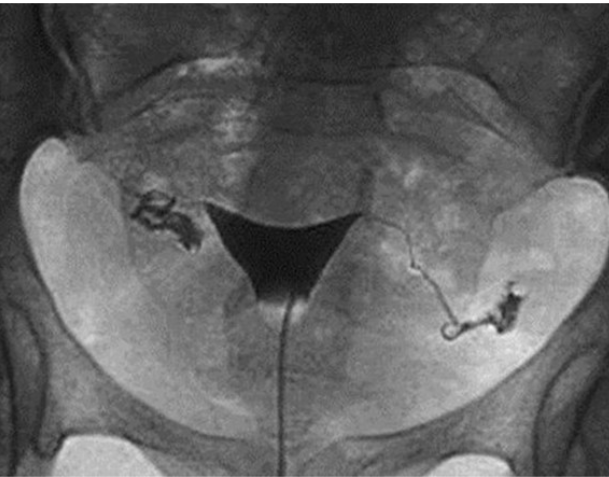

What contrast procedure was performed to produce this image?

Hysterosalpingogram (HSG)

1) contrast procedure performed?

2) contrast media used?

3)What will the doctors be trying to rule out from this examination?

1)Hysterosalpingogram (HSG)

2)Water-Soluble Iodinated Contrast

3)Uterine and Fallopian Tube Abnormalities